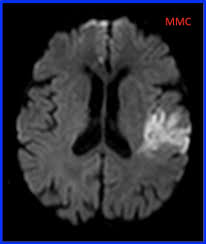

IRM cérébrale: L’ischémie apparait comme un hypersignal (blanc) en séquence de diffusion (autres séquences = FLAIR et perfusion)